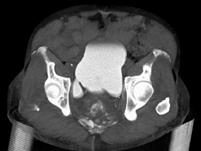

男,67岁,排尿困难1年余,加重1个月,请结合下列图片作出诊断 ( )A、膀胱结核B、膀胱炎C、输尿管囊肿D、膀胱结石E、膀胱憩室

问题 男,67岁,排尿困难1年余,加重1个月,请结合下列图片作出诊断 ( )

选项 A、膀胱结核 B、膀胱炎 C、输尿管囊肿 D、膀胱结石 E、膀胱憩室

答案 E